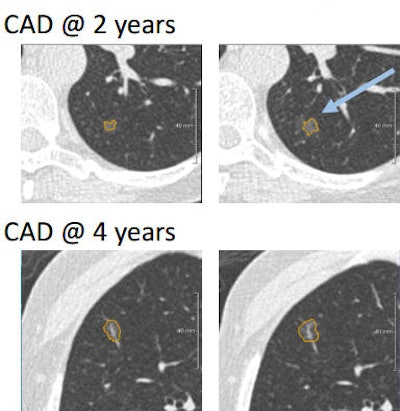

Nearly half of subsolid nodules initially missed by CAD (top row) were detected in subsequent screening rounds (bottom row). No subsolid nodules missed by CAD became cancer.In total diameter, there was good correlation been manual and semiautomated measurements, and in the diameter of the solid components. Still, CAD tended to overestimate the solid components of part-solid nodules, a potentially important shortcoming due to the importance of the solid component in assessing malignancy risk.